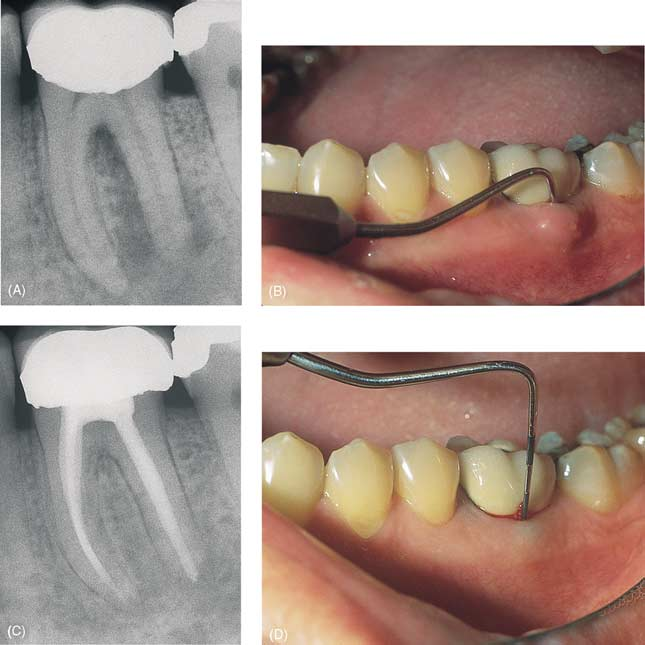

其实,一般情况下牙龈上的这种小包是因为牙齿炎症形成脓液,然后脓液从牙龈处穿破排出而形成的一个通道,专业术语称为窦道[1]。这种情况的患者大多数在牙龈出现“小包”之前都经历过牙齿疼痛,待“小包”出现之后疼痛反而缓解,那是因为脓液排出,炎症压力释放,疼痛才得到了缓解。所以牙龈“长包”,不要惊慌,及时就医,大多数情况下对牙齿进行“根管治疗”,都会获得良好的效果。